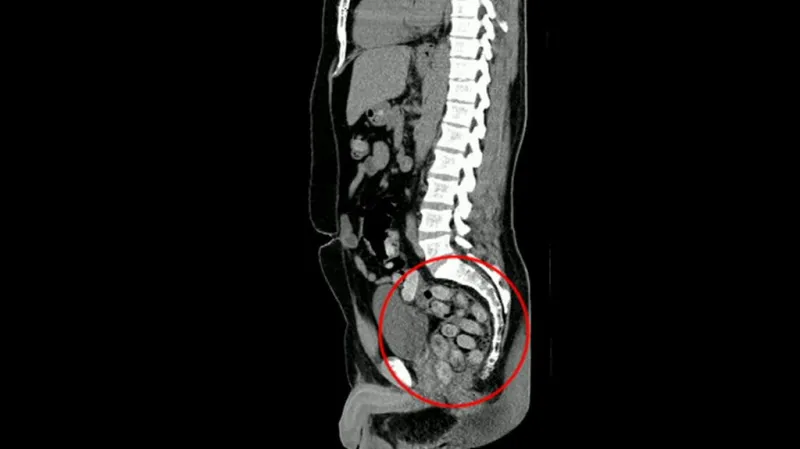

Už 10 měsíců tráví v brazilském vězení také dvacetiletá Michala Potocsková. O loňských prázdninách, po dokončení studií, rodičům oznámila, že cestuje se skupinou kamarádů na dovolenou do Španělska. Její přítel prý dostal vysoké odměny v zaměstnání a všechno jí zaplatí. Na jihu Evropy ale náhle plány změnila a ozvala se z Brazílie. Po několika dnech už byl její mobilní telefon nedostupný. Celníci ji zadrželi na letišti spolu s přítelem, který měl ve falešném dně kufru ukryto skoro osm kilogramů kokainu, o kterých neměla tušení.